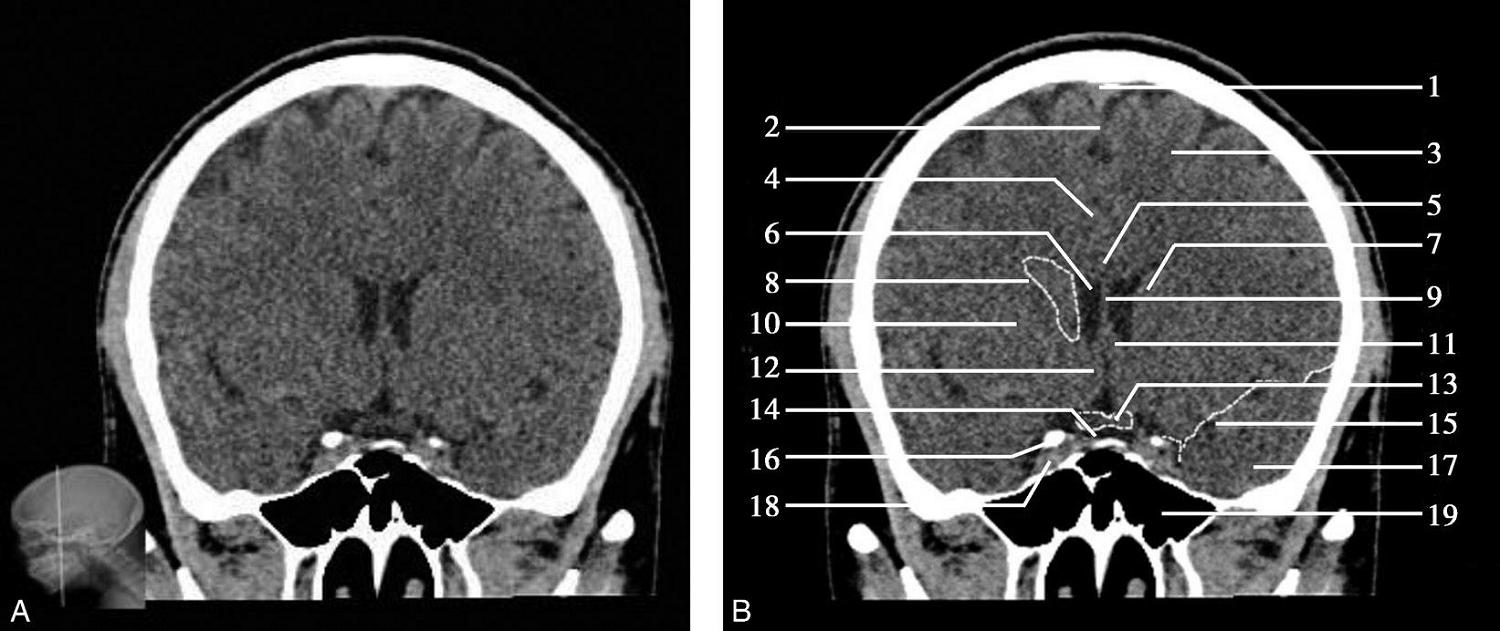

图1-2-10 蝶鞍层面

A.横断面;B.横断面标注

1.额窦;2.眼球;3.筛窦;4.颞肌;5.额底;6.蝶窦;7.颞叶;8.垂体;9.海绵窦;10.基底动脉;11.脑桥;12.第四脑室;13.乳突;14.乙状窦;15.小脑半球;16.小脑蚓部;17.窦汇

图1-2-11 蝶鞍层面(骨窗)

1.额骨眶突;2.鸡冠;3.蝶骨大翼;4.蝶鳞缝;5.蝶骨小翼;6.后床突;7.鞍背;8.颞骨鳞部;9.乳突;10.枕乳突缝;11.枕骨;12.枕内隆凸

层面前部为额骨,额骨中部可见横行的含气腔隙为额窦,中间有骨板分隔,两侧额窦窦腔大小可不一致。额窦外侧为尖朝向后内的锥形眼眶,其内前部为眼球,眼球后方为眶脂体。两眼眶之间正中为鸡冠,其两侧为前颅窝底及其内的额叶底部断面,再外侧为筛窦。前颅窝底的后方为蝶骨体,其内中部可见蝶窦,蝶窦后外侧为蝶骨小翼,后方为前床突,左右前床突之间为鞍结节,鞍结节与鞍背之间为垂体窝,内有脑垂体,后床突居鞍背两端。

蝶鞍两侧为海绵窦,其内包含颈内动脉及第Ⅲ~Ⅵ对脑神经。海绵窦的密度升高或体积增大常提示病变存在。海绵窦外侧为颞叶,两者之间隔以海绵窦外侧壁。鞍背后方为桥前池及其后方的脑桥,桥前池内可见基底动脉断面,呈圆形稍高密度影。层面中部两侧为颞骨乳突部,其内气化的骨性腔隙为乳突气房。脑桥后方为第四脑室,呈半圆形或新月形,小脑半球的病变(如肿瘤、炎症、出血等)常压迫第四脑室,导致其变形甚至闭塞(图1-2-13)。两侧小脑半球间为小脑蚓部。小脑半球与颞骨乳突部间可见乙状窦。小脑蚓部后方为直窦与上矢状窦汇入窦汇处,窦汇两侧为横窦。静脉窦血栓时可见上述静脉窦增宽、密度明显升高(图1-2-14)。